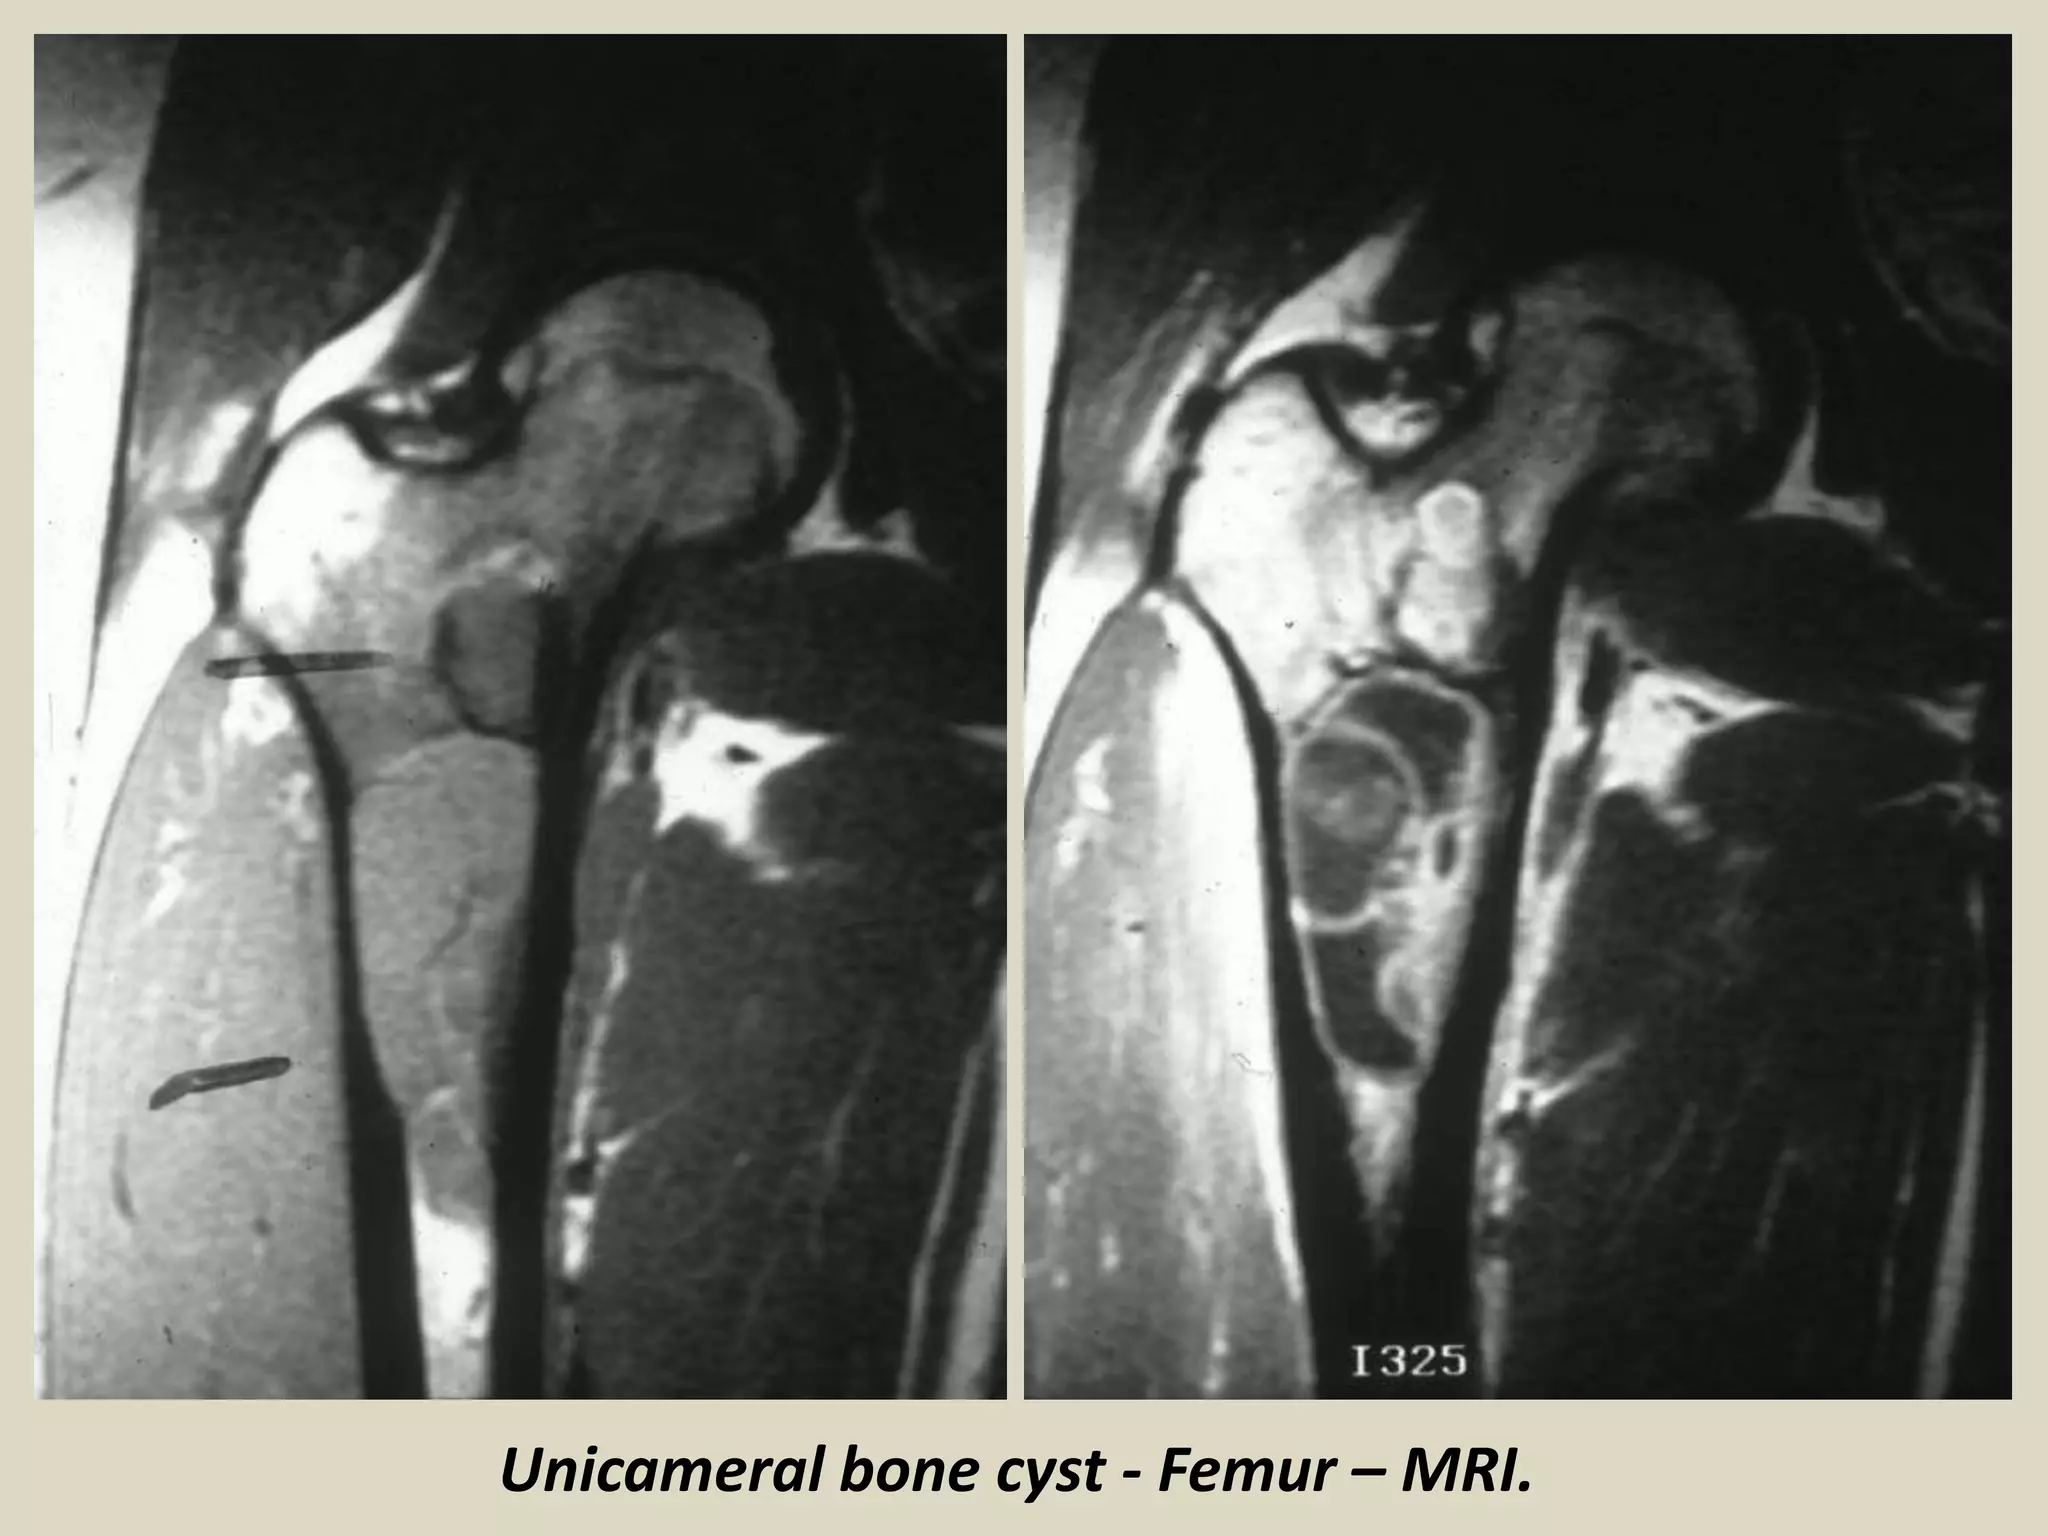

SIMPLE (UNICAMERAL ) BONE CYST (UBC)

- Intramedullary, usually unilocular, bone cyst filled with

serous or sero-sanguineous fluid.

- 85% of patients in the first decades of life.

- Male: Female ratio 3:1.

- Most common locations:

- proximal humerus

- proximal femur

- proximal tibia

- Pain and swelling.

- Patients may present with pathological fracture.

- Well demarcated and radiolucent.

- Typically begins in the metaphysis and extends into the diaphysis.

Gross:

- Fragments of thin whitish membrane

- Usually during surgery you get scant tissue material.

SIMPLE (UNICAMERAL ) BONE CYST (UBC).

Unicameral bone cyst - Femur – MRI.